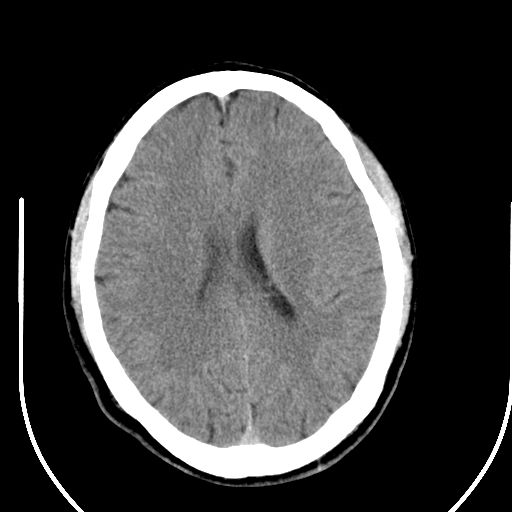

标题: CT25423:头部外伤意外发现右顶叶??? [打印本页]

标题: CT25423:头部外伤意外发现右顶叶???

ct值约13hu。

边缘清晰,没有占位效应,不像脑沟,结合ct值,软化灶可能吧

与脑沟没关系,小软化灶或陈旧性感染吧!

看样年纪不小了直接报腔梗,当然你要想报软化灶也是一样的

考虑右侧额叶巨腔隙灶;建议必要时行mri检查。